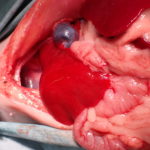

先天性心嚢横隔膜ヘルニア

若い猫が、普段はとても元気だけど、遊んだ後などに咳をする。呼吸が早くなる時がある。などの呼吸器症状で主治医を受診しました。エックス線検査の結果、心嚢横隔膜ヘルニアと診断されました。主治医より、外科的な対応のため紹介受診となりました。腹部正中切開の後、心嚢内に逸脱した、肝臓、胆嚢、小腸を腹腔内に戻し、横隔膜を再建しました。術後には、再拡張性肺水腫という病態が発生する可能性があるため、24時間体制で、患者さんを見守ります。幸い、肺水腫の傾向はみられず、5日目に無事に退院となりました。周術期には一時的に低酸素症に陥ったり、二酸化炭素濃度が上昇したりと、不安定な場面もありましたが、小さな体で本当によく頑張ってくれました。これで、普通の子猫としてどんどん大きく成長してくれると思います。本当によかった。